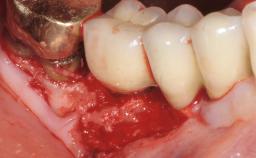

Treatment of Peri-Implant Mucositis at a Zirconia Implant

Recent clinical studies, most with short-to-medium term observation periods, have reported on the favorable clinical performance of zirconia implants in terms of survival rates, clinical, and radiographic outcomes (Roehling and coworkers 2016; Roehling and coworkers 2017; Rodriguez and coworkers 2018; Lorenz and coworkers 2019). Nonetheless, a rather high incidence of peri-implant disease at zirconia implants (39% of implants) was noted throughout a two-year period, highlighting the need for treatment protocols of peri-implant diseases at zirconia implants (Becker and coworkers 2017).